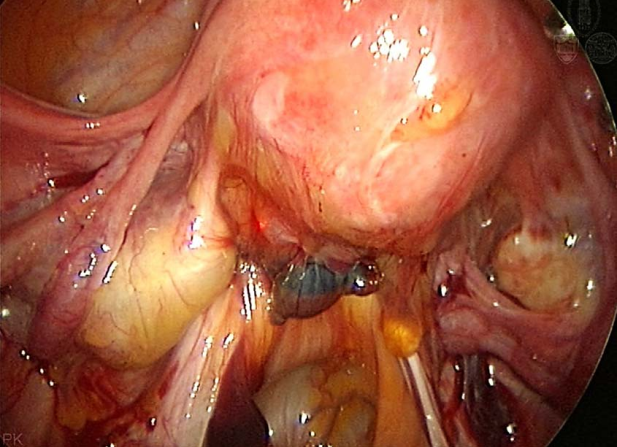

卵巢巧克力囊肿腹腔镜下表现